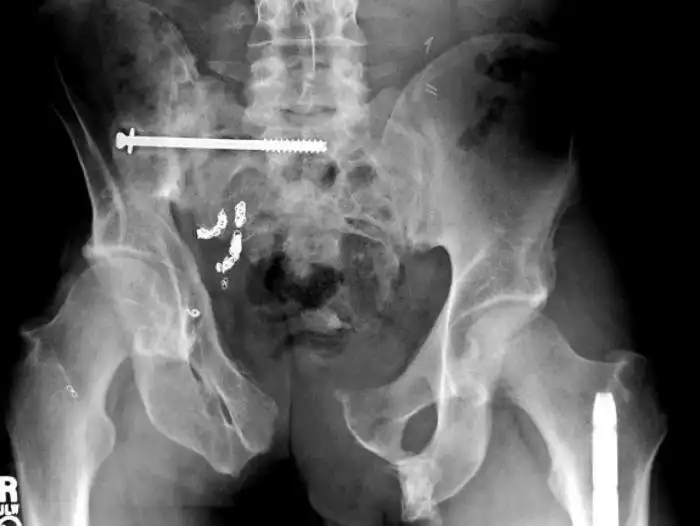

Необычные предметы в теле людей на рентгеновских снимках

На рентгеновских снимках людей порой можно обнаружить самые необычные предметы, которые находятся в их теле.